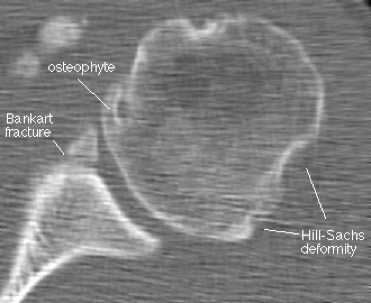

Наиболее типичным (около 85% передних смещений травматической этиологии) является повреждение Банкарта - отрыв фиброзного или фибрознохрящевого фрагмента от края суставной впадины в месте прикрепления связки к суставной впадине с повреждением суставной губы. Кроме того, травма может приводить и к костным повреждениям - перелому гленоидного кольца спереди, костному повреждению Банкарта (то есть повреждению Банкарта в сочетании с переломом) и перелому большой бугристости.

МРТ плечевого сустава. Корональные Т1-взвешенные МРТ. Переломы Хилла-Сакса и Банкарта.

Рентгенография, хотя и не позволяет выявлять разрывы связок и суставной губы, остаётся обязательным диагностическим методом при травме плечевого сустава. Она позволяет обнаруживать переломы и костные дефекты, смещения, свободные фрагменты.

На КТ хорошо видны костные дефекты и дефекты гиалинового хряща суставной впадины. Гиалиновый хрящ, покрывающий головку плечевой кости виден гораздо хуже.

КТ плечевого сустава, Переломы Банкарта и Хилла-Сакса.